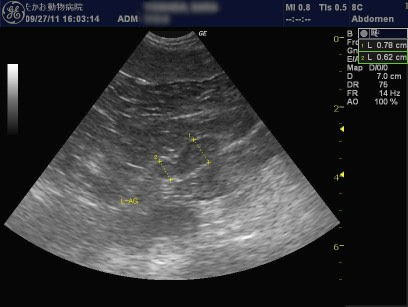

下記のエコー像は最近、当院にて副腎機能亢進症と診断した症例のものです。副腎の厚さが増加しているのが分かります。(特に右)